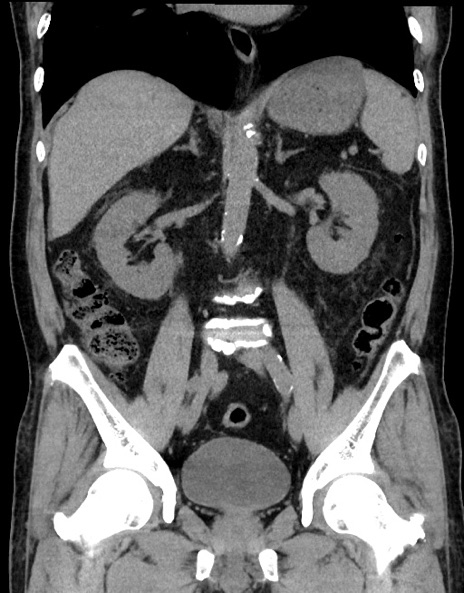

症例15(冠状断像)

【症例】70歳代男性

【主訴】腹痛

【現病歴】今朝から腹痛あり。全体的に痛い。特に左上の方。排ガスが今日はない。冷や汗が出る。

【既往歴】直腸癌術後

【身体所見】左側腹部〜上腹部に圧痛あり。腹膜刺激症状明らかなではない。軽度反跳痛。左下腹部に術後瘢痕あり。

【データ】WBC 7700、CRP 0.02